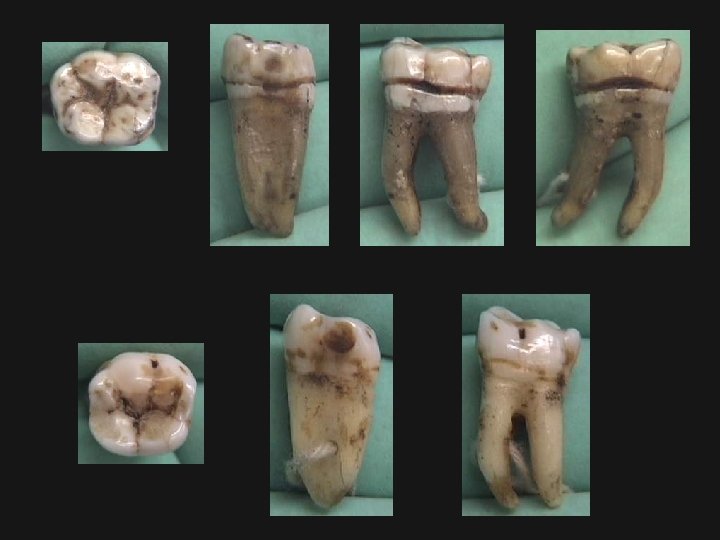

Let’s look at some examples. . .